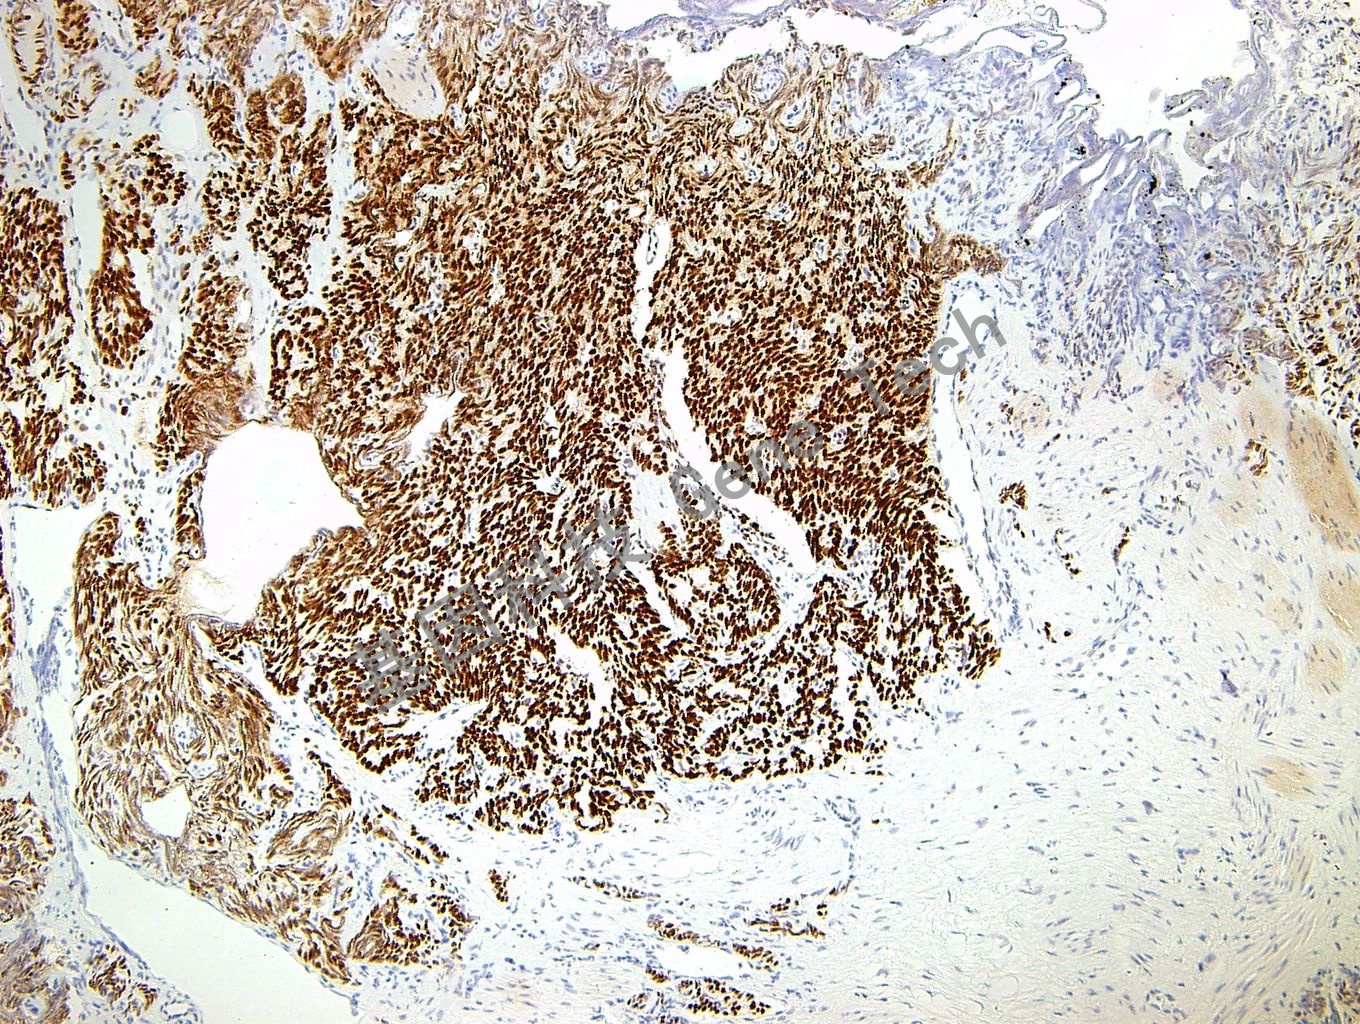

前列腺癌石蜡切片,用 TLE-1(GT2239)染色,细胞核阳性,DAB显色。(10×)